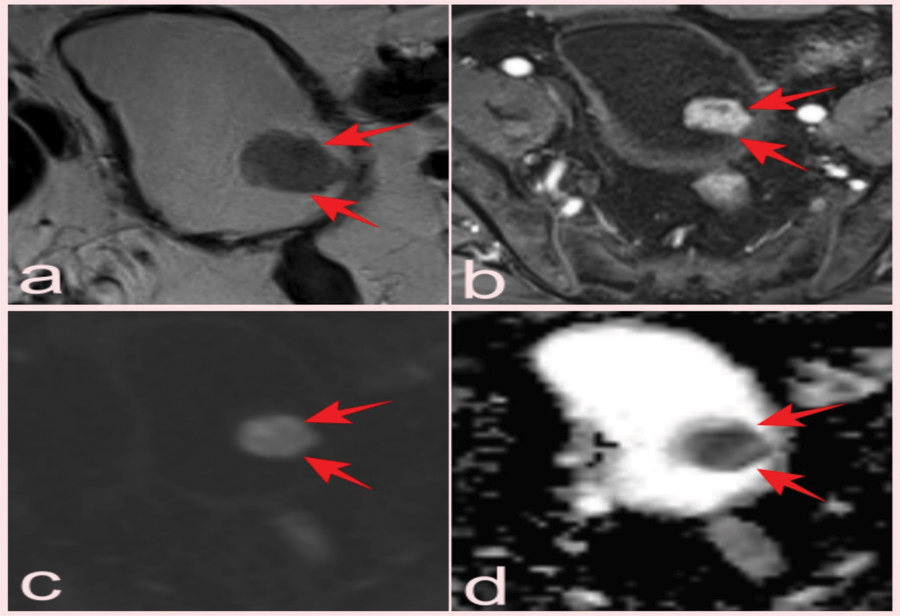

Figure 3

(a) Hypointense soft tissue showing bladder invasion on axial T2-WI in a 74-year-old man with Gleason score 3+4 prostate cancer (arrows). (b) Prostate mpMRI in a 66-year-old patient showed a 0.5 cm lesion on the right posterolateral wall of the bladder that was missed on conventional images but was detected by contrast uptake on DCE images and reported as VI-RADS 1; pathology was benign (Inflamed urothelial tissue) (arrows). T2-WI (c) and DCE (d) images of a 64-year-old patient with a high-grade pT2 tumor classified as VI-RADS 4 (arrows).